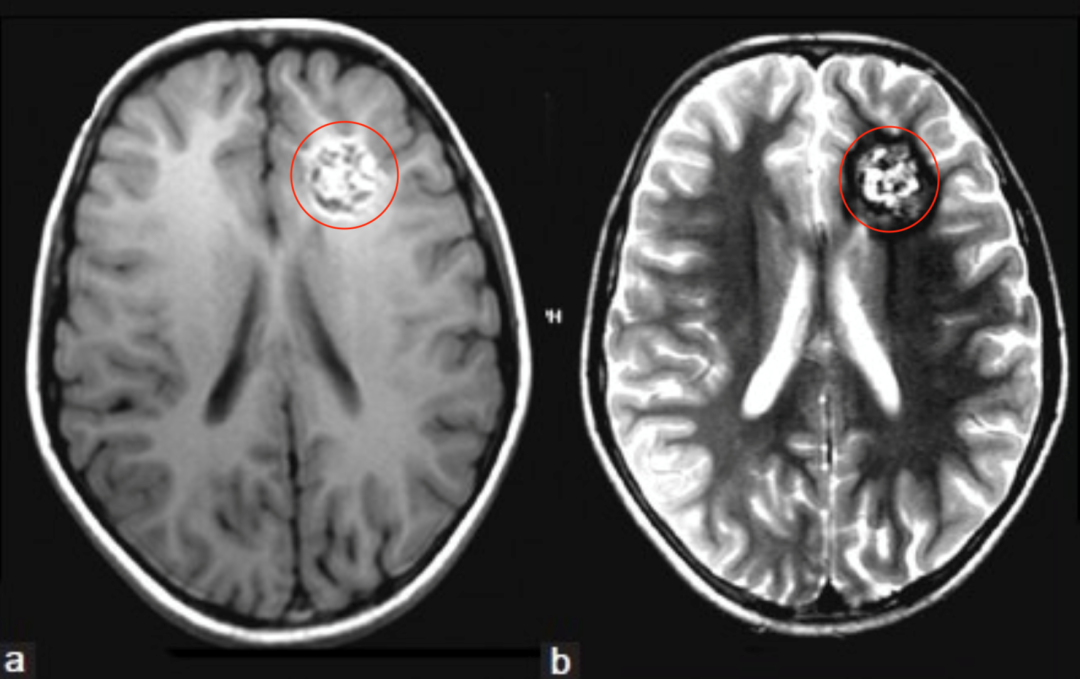

患者情况:9岁女童有多次全身性强直阵挛性癫痫发作及头痛持续6个月之病史。CT平扫显示左侧额叶深部钙化灶。MRI脑T1、T2、FLAIR像显示左额叶深部异质性病变[图2a和b]。根据这些发现,诊断海绵状血管瘤伴顽固性癫痫发作。

图:(a)和(b) MRI T1W、T2W轴位图像显示混合信号的网状核心,代表不同退化状态的血液,注意T2W图像(b)中含铁血黄素的低聚晕